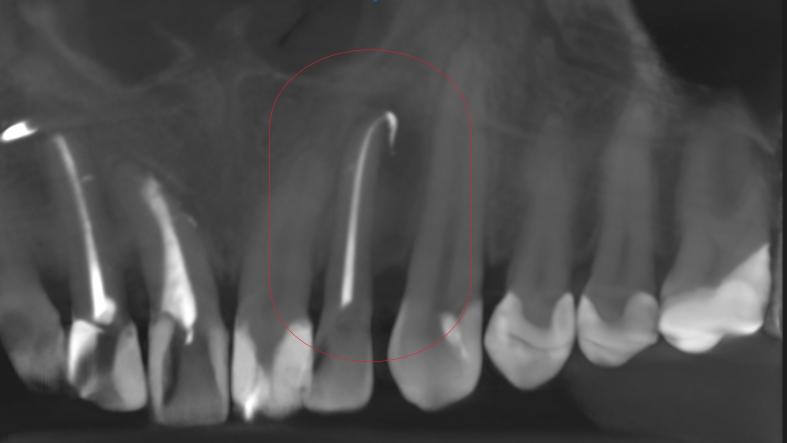

Leczenie kanałowe jest leczeniem skutecznym. Prawidłowe leczenie kanałowe sprawia, że ząb przestaje być ogniskiem zakażenia, a tkanki wokół goją się. Wyleczenie zęba powoduje, że przyczyna choroby tkanek około zębowych [na RTG widzimy jedynie chorobę kości] zostaje usunięta. Eliminacja przyczyny choroby umożliwia gojenie się zmian chorobowych.

Na poniższych zdjęciach RTG – WIDAĆ GOJENIE ZMIAN ZAPALNYCH KOŚCI.

Nie jest prawdą, że leczenie kanałowe w każdym przypadku jest szkodliwe. Ogniskami zakażenia są zęby martwe, nieprzeleczone kanałowo, zęby z nieprawidłowym leczeniem kanałowym i to właśnie one są zagrożeniem i powinny być eliminowane.